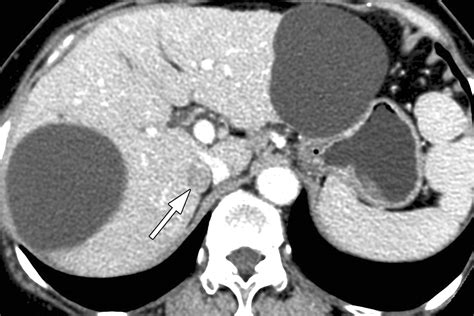

• Imaging Tests: Computed tomography (CT) scans and magnetic resonance imaging (MRI) are commonly used to visualize the adrenal glands and detect tumors. These tests can provide detailed images of the adrenal glands and help determine the size and characteristics of the tumor.